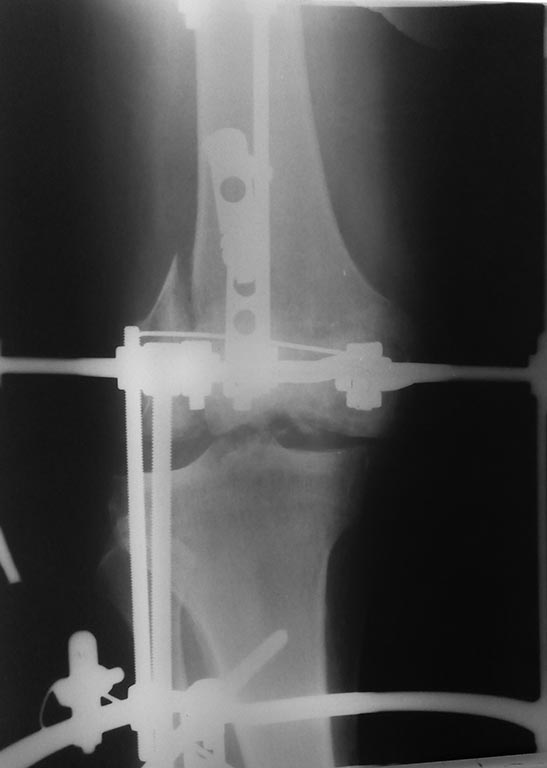

пациент 57 лет. травма в октябре 2016г. ДЗ: Открытый вывих правой голени

с переломом наружного мыщелка бедренной кости. при поступлении

произведено ПХО раны, открытое вправление, наложение аппарата внешней

фиксации. в настоящее время раны зажили без воспалительных

явлений.имеется смещение отломка наружного мыщелка. нужна помощь в

определении тактики дальнейшего лечения.